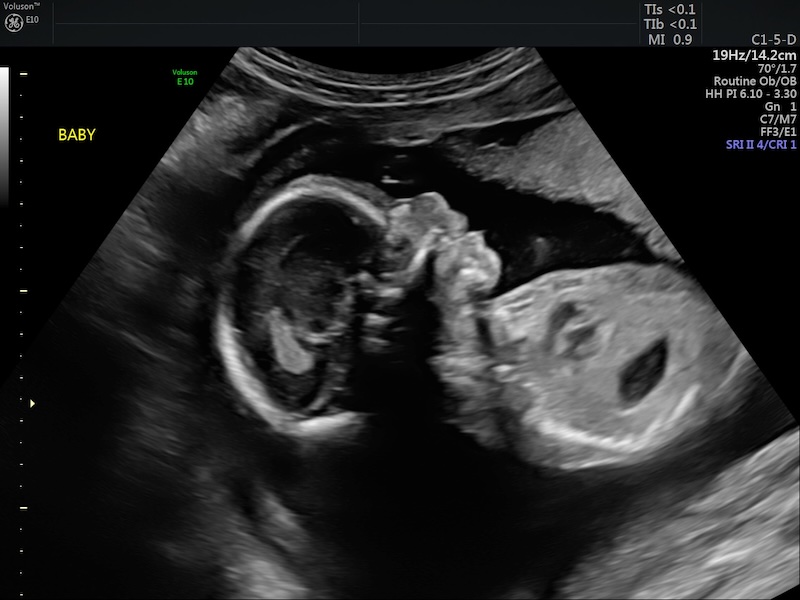

Halfway, The Anatomy Scan, and All The Emotions